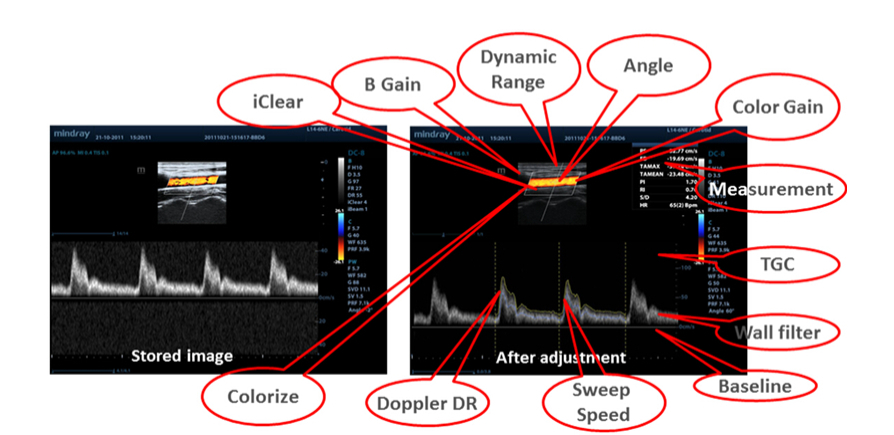

Dati grezzi

Consente una flessibilit├Ā ottimale per la post-elaborazione delle immagini salvate, compresi adattamenti dei parametri, aggiunta di commenti e misure e massima produttivit├Ā durante la scansione.